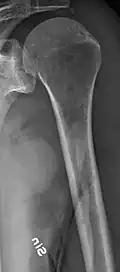

The diagnostic examination of a person with suspected multiple myeloma typically includes a skeletal survey. This is a series of X-rays of the skull, axial skeleton, and proximal long bones. Myeloma activity sometimes appears as "lytic lesions" (with local disappearance of normal bone due to resorption) or as "punched-out lesions" on the skull X-ray ("raindrop skull"). Lesions may also be sclerotic, which is seen as radiodense.[76] Overall, the radiodensity of myeloma is between −30 and 120 Hounsfield units (HU).[77] Magnetic resonance imaging is more sensitive than simple X-rays in the detection of lytic lesions. An MRI may supersede a skeletal survey, especially when vertebral disease is suspected. Occasionally, a CT scan is performed to measure the size of soft-tissue plasmacytomas. Nuclear Medicine Bone scans are typically not of any additional value in the workup of people with myeloma (no new bone formation; lytic lesions not well visualized on nuclear bone scan).

Multiple myeloma in the upper arm -

Femur with multiple myeloma lesions -

Humerus with multiple myeloma lesions -